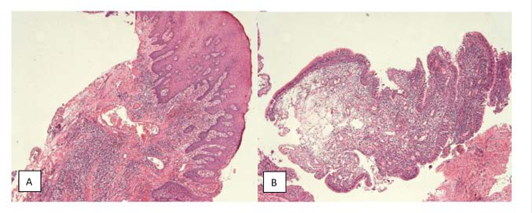

A 33-year-old man reported an episode of bleeding in the mouth and extravasation of fluid through the nose during liquid ingestion. The bleeding occurred in the upper right first molar region over one year, and there was extravasation of blood and serous fluid through the nose associated with pain and pressure on the same side of the face, when the patient was yawning. The medical condition did not show any comorbidity. In the intraoral exam, a 7mm periodontal pocket was detected. A gingival recession was also observed around the UFM and a Valsalva test was negative. The panoramic x-ray showed vertical bone loss in the super right first and second molar (URFSM) region. There was a bilateral alveolar ex-tension of maxillary sinus with opacification on the right maxillary sinus only (figure 2). We prescribed a CBCT exam, which showed severe furcation in-jury, external root reabsorption and vertical bone loss around cortical floor, and a thickening of the sinus mucosa around the URFSM. There was a rupture in the floor of the cortical sinus (figure 3). The diagnostic hypothesis was OMS related to periodontal disease or maxillary sinus tumor of the maxillary sinus floor. The extraction of the URFSM was done with curettage of the soft tissue associated with dental roots. In the surgical procedure, a 1cm diameter oroantral communication was observed, treated with intra alveolar fibrin sponge covered with a vestibular flap of oral mucosa (figure 4). The microscopic analysis showed no signs of malignancy and chronic inflammatory cell infiltrate compatible with inflammatory periodontal disease (figure 5). The final diagnosis was odontogenic maxillary sinusitis related to periodontal disease. A corticosteroid nasal spray was prescribed, and three months after the surgical procedure no clinical signs or symptoms were observed. A new panoramic x-ray six months after the surgical procedure showed normal radiopacity of the right maxillary sinus (figure 6).